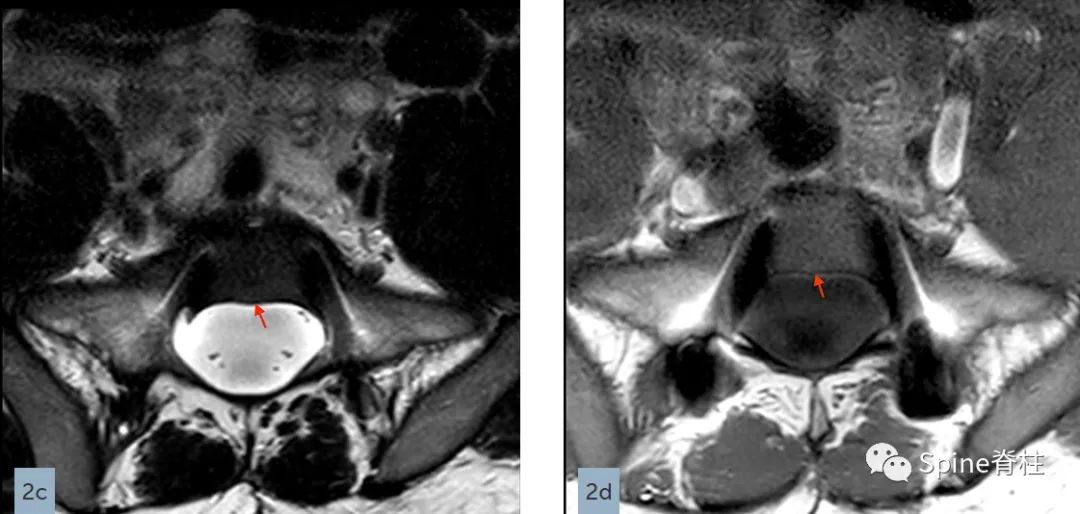

测量L5处的最大神经根袖直径 (nerve root sleeve diameter) 。请注意,神经根袖的直径右侧为7.3 mm,左侧为4.5 mm。因此,L5神经根袖的最大值为7.3 mm,这符合次要标准之一。只有当最大值超过6.5 mm时,才满足L5神经根袖直径的次要标准。